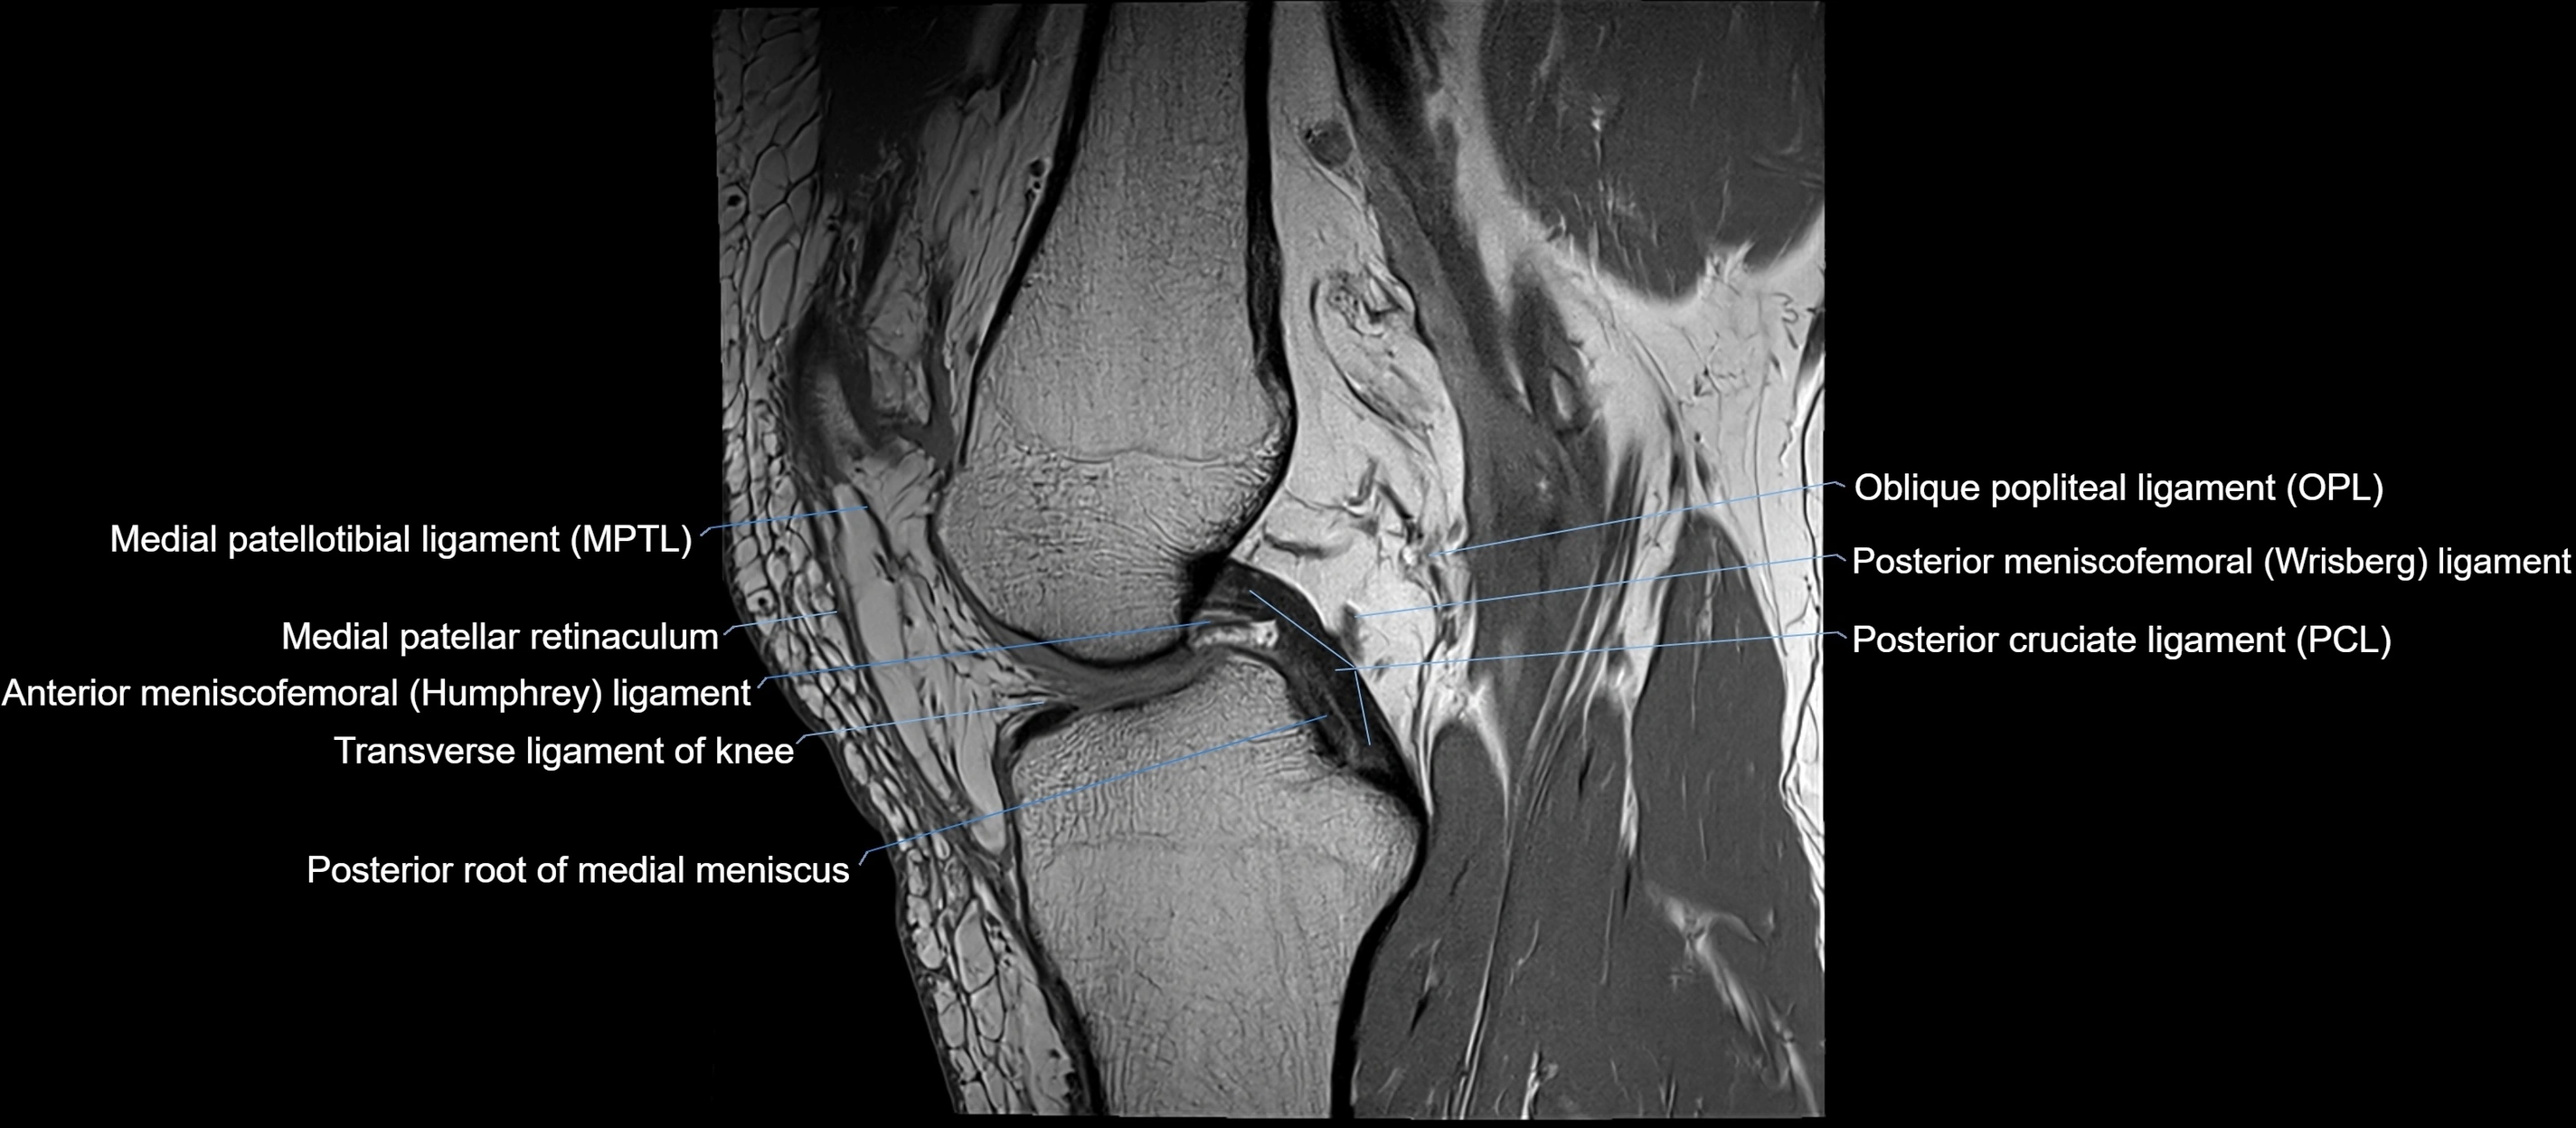

MRI Appearance

T1-weighted images:

• Normal ACL appears as a low-signal band-like structure crossing the intercondylar notch

• Surrounded by intermediate signal synovial fluid and fat planes

T2-weighted images:

• Normal ACL remains low signal

• Partial or complete tears appear as discontinuity, increased signal, or fiber laxity

STIR (Short Tau Inversion Recovery):

• Normal ACL shows dark low signal

• Acute injury shows bright hyperintensity due to edema and hemorrhage

Proton Density Fat-Saturated (PD FS):

• Normal ACL: dark, low-signal band

• Tears: bright intraligamentous hyperintensity, discontinuity, or abnormal course

MRI images

image